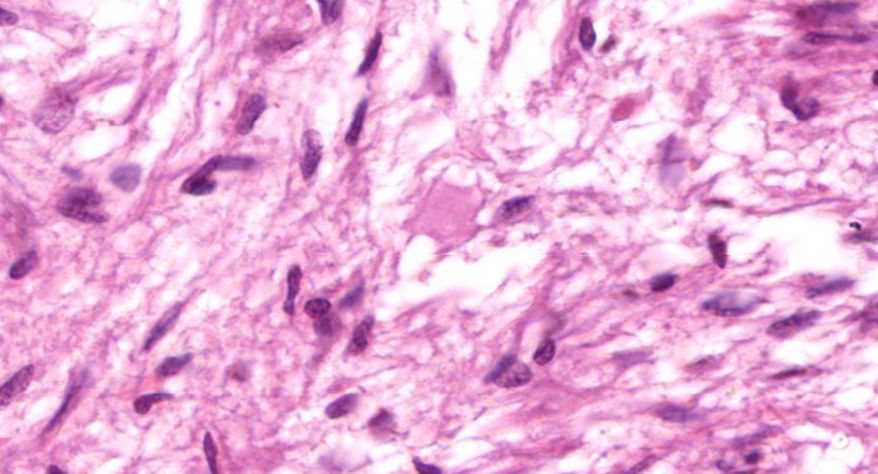

糖尿病肾病:1.大部分肾小球系膜区大量基质增多,较多形成结节状扩大,少数细胞靠结节边缘排列, 形成典型的K-W结节。部分节段有系膜细胞轻度增生, 基膜增厚。2.少数小球伴有球囊壁纤维化。 少部分肾小球硬化(玻璃样小体)。3.肾小管较多灶性萎缩,部分肾小管扩张,管腔内有蛋白管型。4.间质广泛纤维化,伴大量炎症细胞浸润(淋巴细胞、浆细胞)。许多肾小球入球细动脉壁增厚玻变, 间质肌性小动脉内膜增厚纤维化。

1.全景图

2.肾小球多个W-K结节形成

3.肾小球硬化

4.肾小管扩张

5.入球微动脉管壁增厚